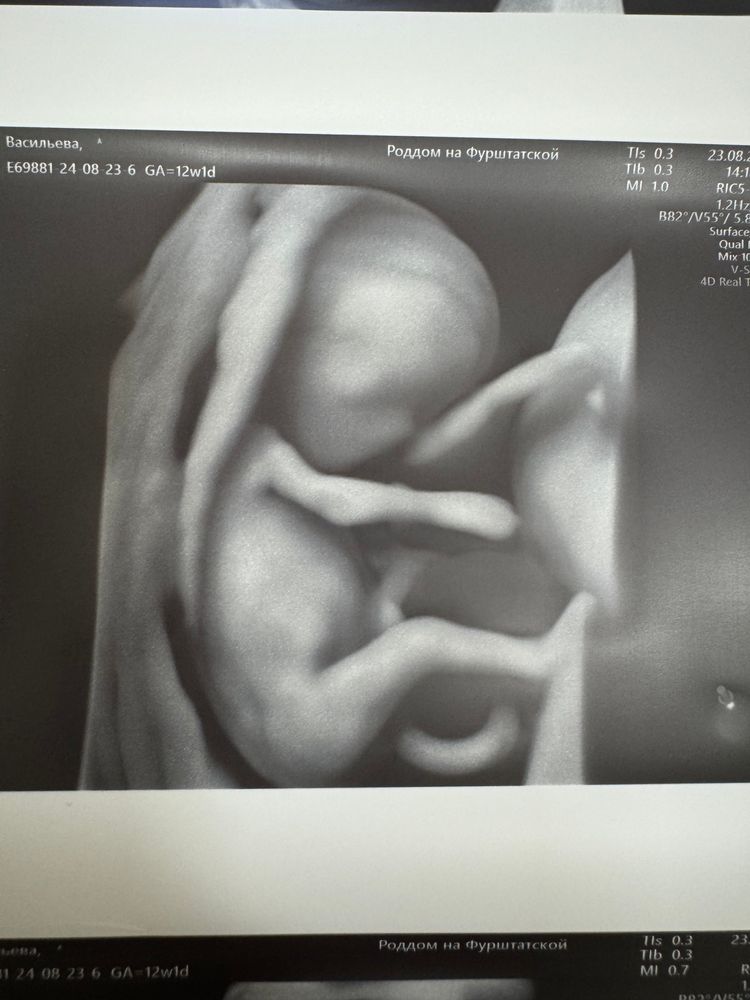

Первый скрининг 😍

Какой милашек! Сколько ж ему? 12-13 неделек?

Екатерина, 12 и 1 день )))